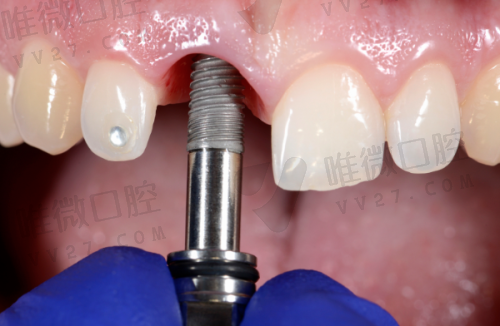

种植牙2980元起,这价格靠谱吗?

乍一听种植牙只要2980元是不是有些惊讶?其实这也是基础种植体品牌——韩国登腾类的价格含义,而且是含种植体+基台+牙冠的“全包价”,没有那些“临时牙、结构费另算”的猫腻。当然,如果你注重美国品牌、德国品牌,也能选,比如3680起的皓圣、8800元起的ITI,明确标注。真正做到了“口袋有多深,牙就种多大”这种按需选择。